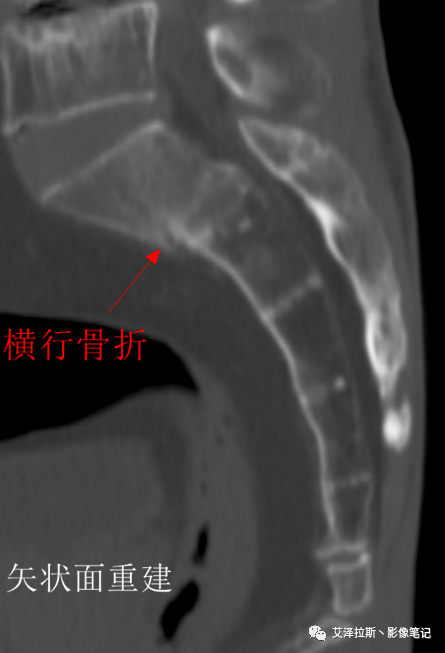

X线、CT:骶骨重度骨质疏松,双侧骶骨翼皮质断裂,分别见迂曲走行的纵行透亮线位于骶孔外侧,大致与骶髂关节间隙平行,骨折端局部可见骨痂、骨质硬化。

X线、CT:

①单侧或者双侧骶骨翼骨折,典型者呈“H”形,即“Honda征”;

②骨折线位于骶孔外侧(如下图,主要发生于1区),通常可能会伴随耻骨的功能不全骨折(如:病例2 右侧耻骨上支骨折,L5双侧横突骨折);

③愈合期骨折线模糊,骨痂形成,骨质硬化;